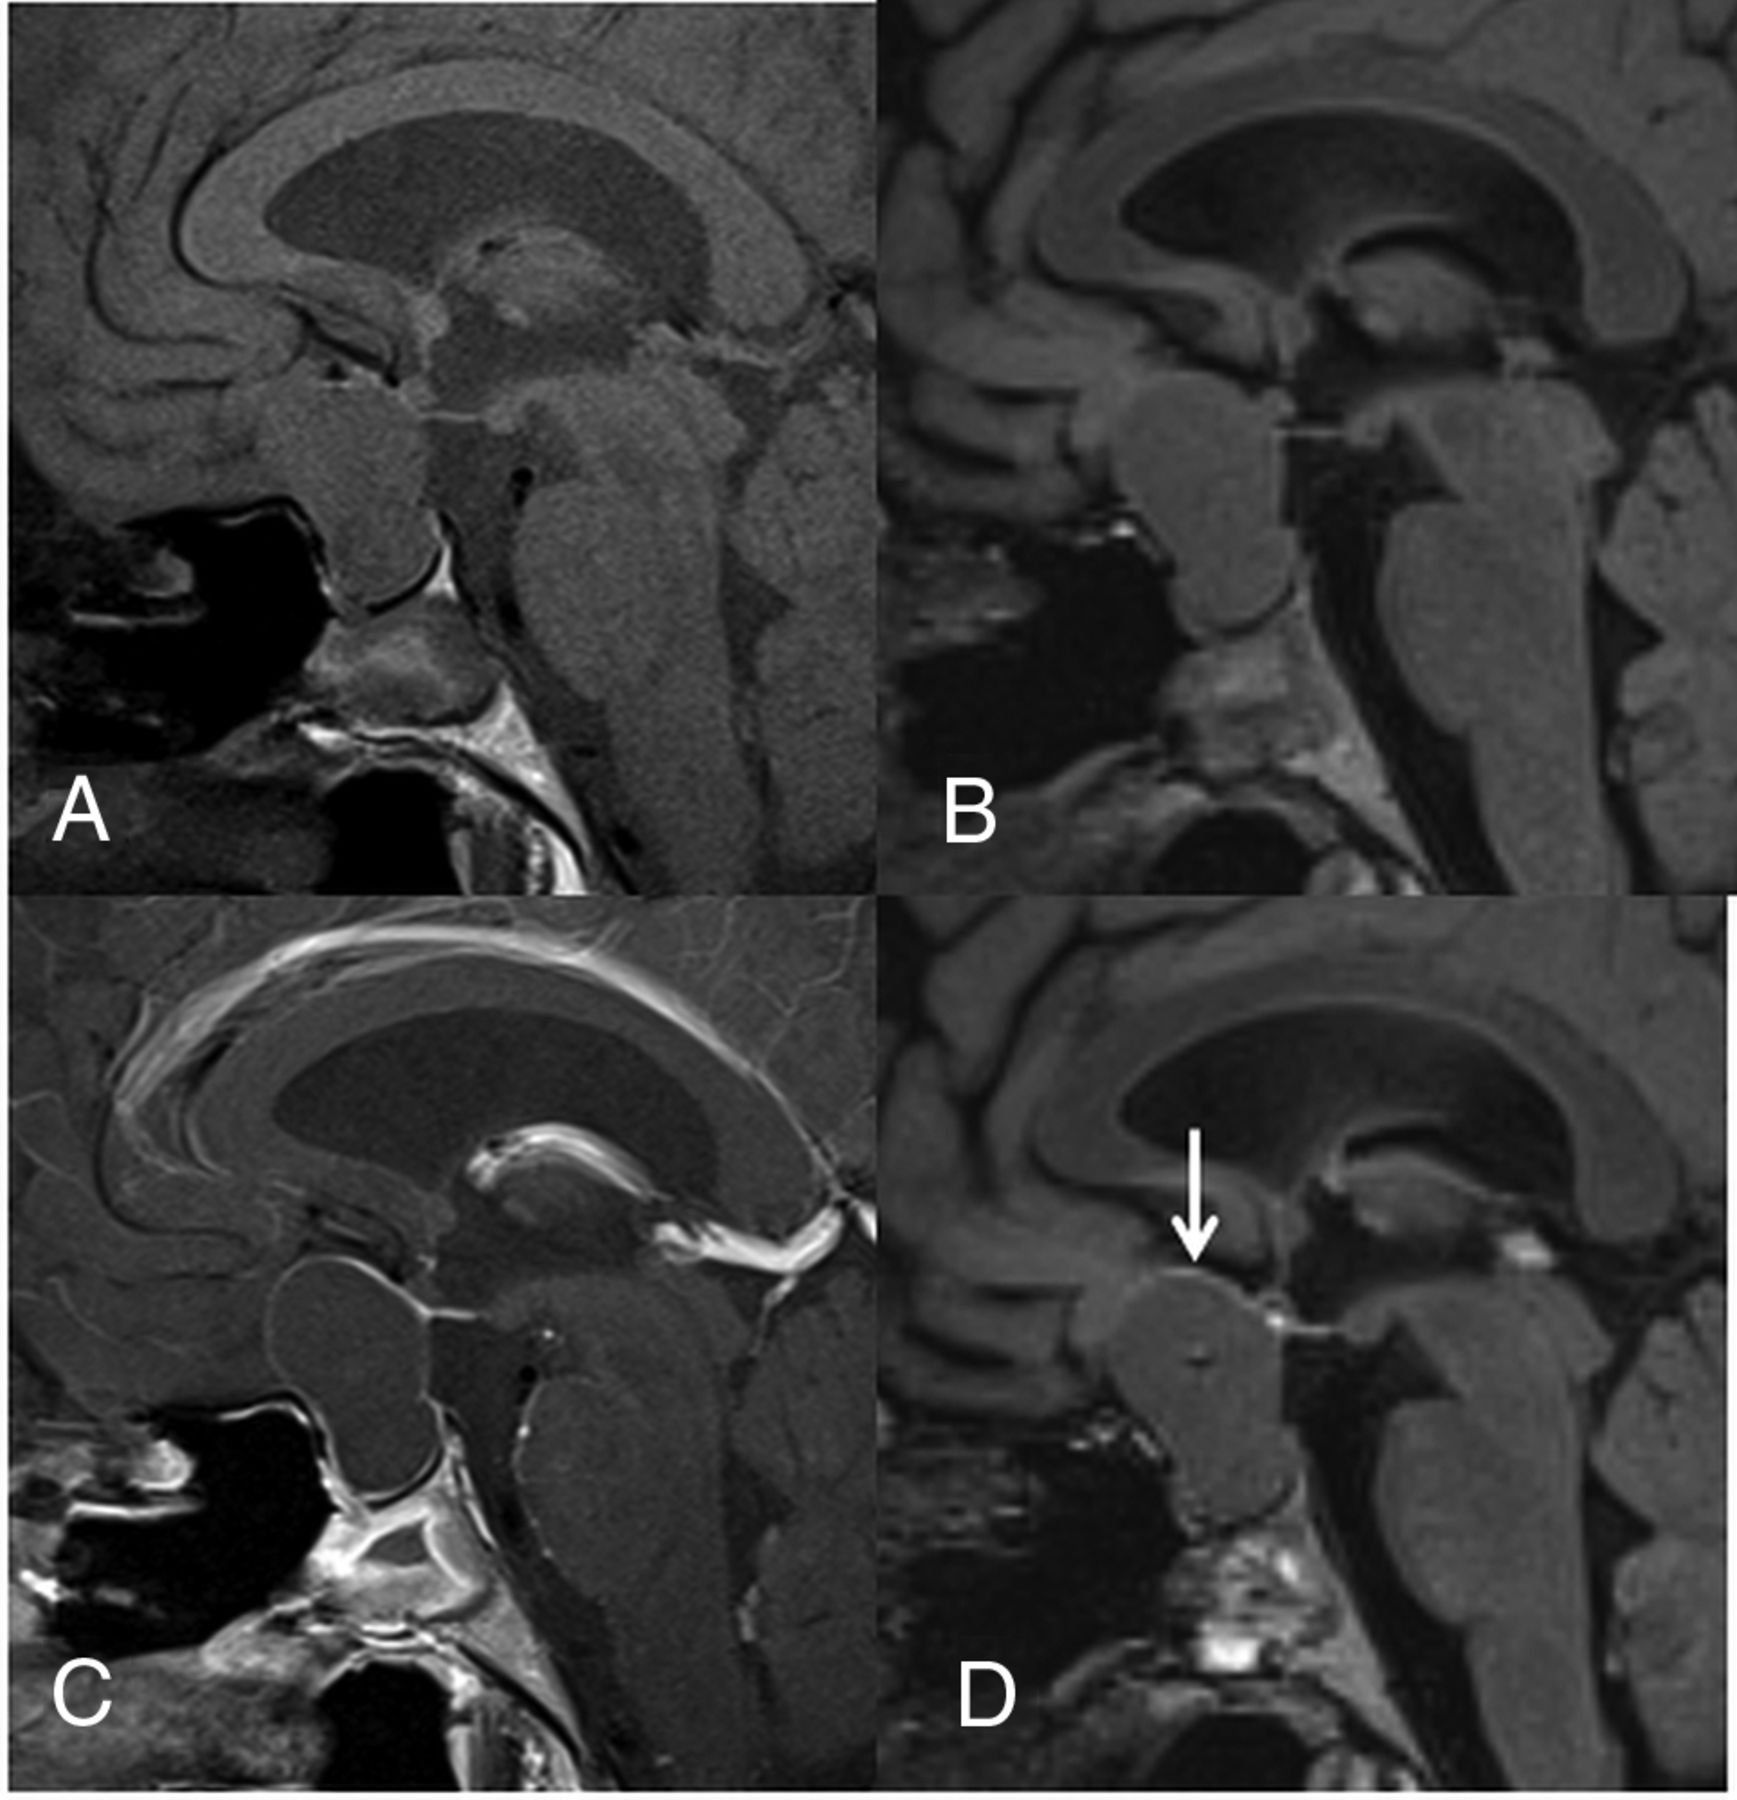

A 44-year-old woman with a CCP. A comparison of pre- (A) and postcontrast T1WI (C) shows that the cyst wall is enhanced on the postcontrast image (grade 2). A comparison of pre- (B) and postcontrast 3D T2-FLAIR images (D) reveals enhancement of the cyst wall (grade 2) and the lesion center on the postcontrast image (D). Different from the postcontrast T1WI (C), the pituitary gland is not intensely enhanced on the postcontrast 3D T2-FLAIR image (arrow in D). The observer judged this lesion as probably an RCC (scale 2) at the conventional MR interpretation, whereas the confidence level was changed to probably a CCP (scale 4) by the addition of 3D T2-FLAIR interpretation.